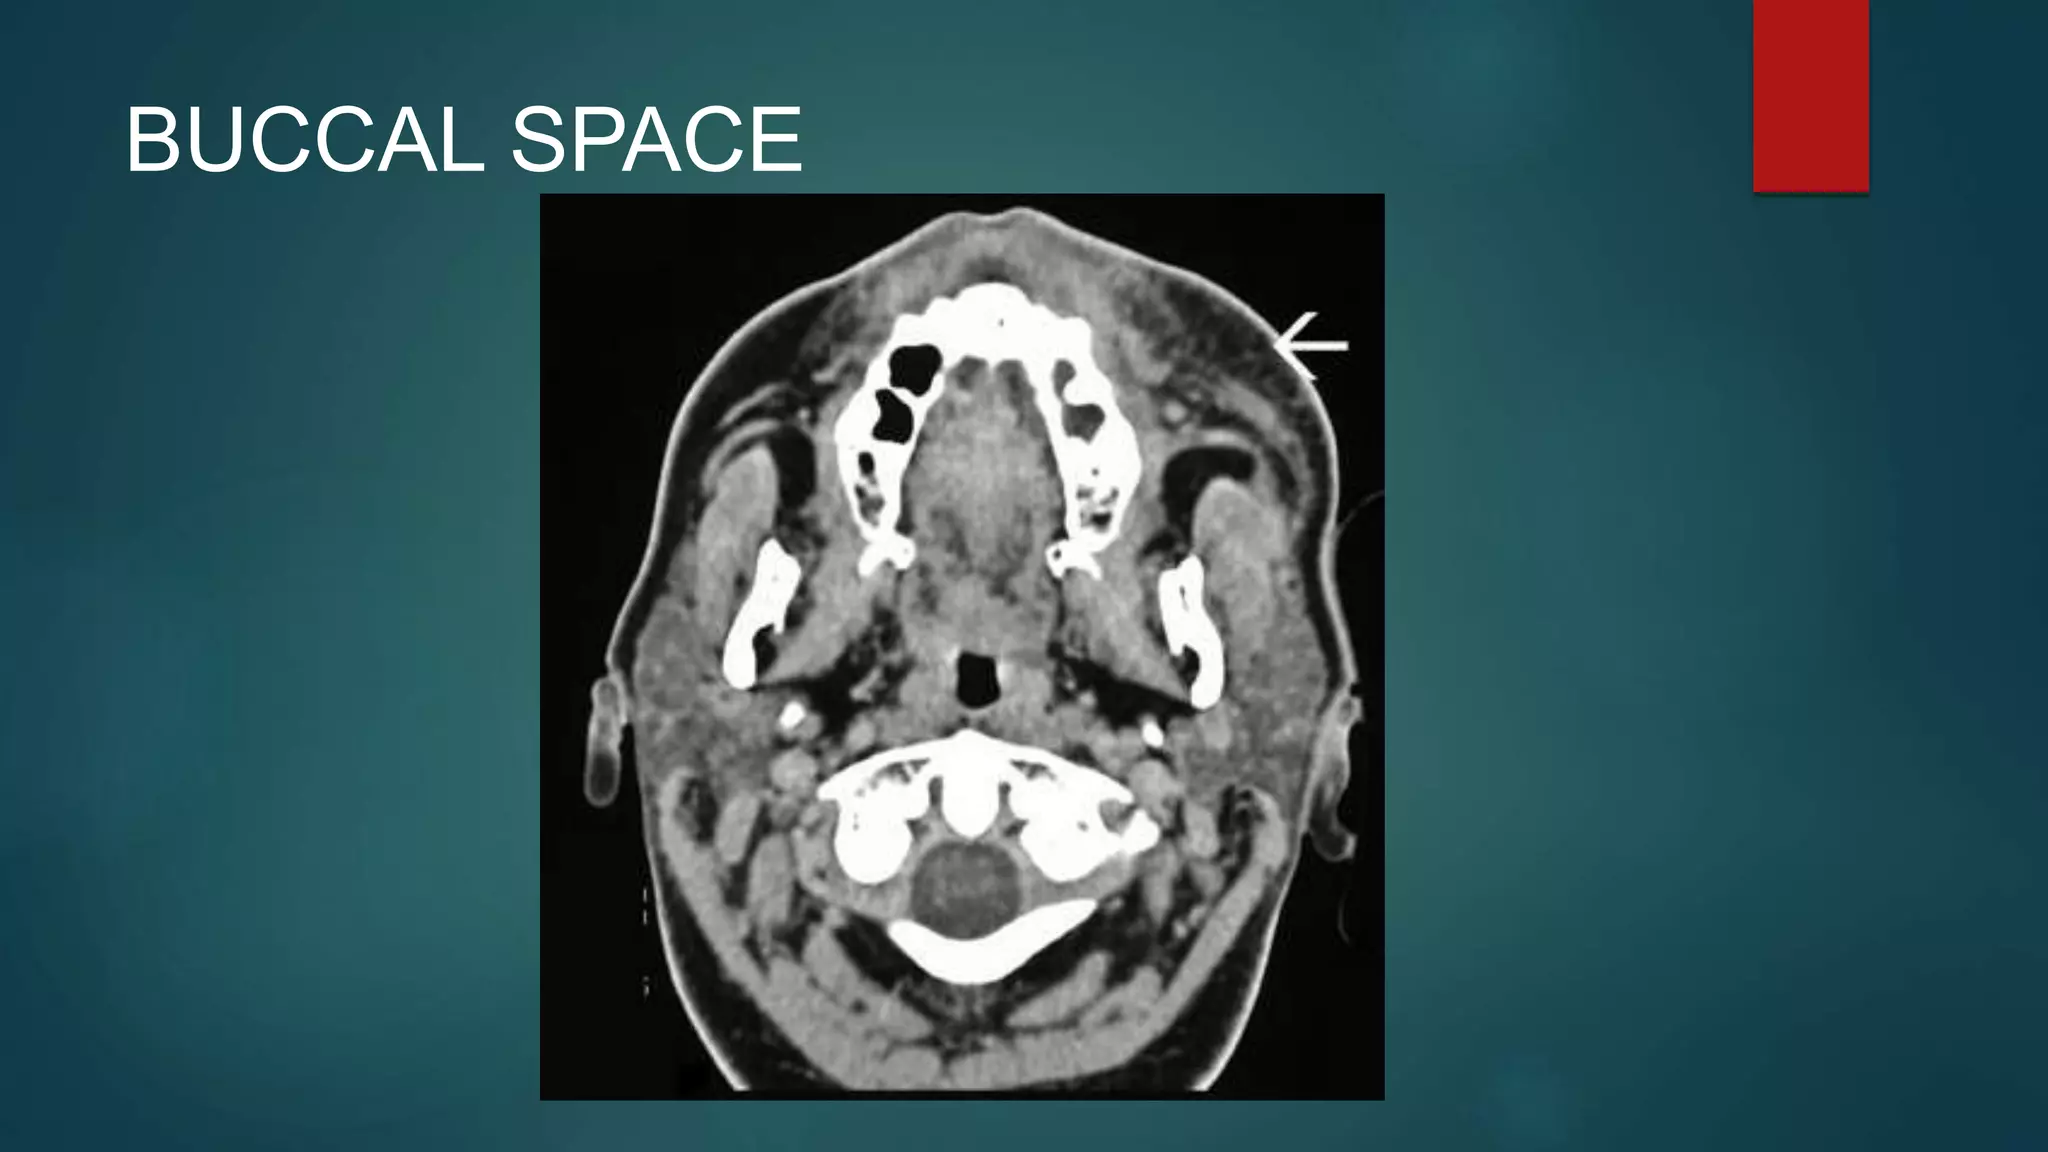

BUCCAL SPACE

 The buccal spaces are paired fat contained spaces on

each side of the face forming cheeks. Each space is

enveloped by the superficial (investing) layer of the deep

cervical fascia.

 Contents

• fat: cheek padding

• parotid duct

• accessory parotid gland in 20% of people which can

cause facial asymmetry; readily seen on MRI

• facial and buccal arteries and corresponding veins

• facial nerve (CN VII): buccal branch

• trigeminal nerve (CN V): buccal branch of the

mandibular division (CN Vc)

 http://radiopaedia.org/articles/buccal-space

 Boundaries and relations

• anterior: orbicular oris muscles and the angle of the mouth

• posterior: masseter muscle, mandible, medial pterygoid and lateral

pterygoid muscles

• superior: zygomatic process of the maxilla and zygomaticus muscles

• inferior: depressor anguli oris muscle and the deep fascia attaching to

the mandible

• medial (deep): buccinator muscle

• lateral (superficial): platysma muscle and subcutaneous tissues with

the skin